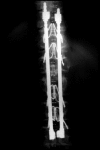

The mean survival of patients with skeletal solitary plasmocytoma is 75% at 5-year follow-up. This highly osteolytic tumor may compromise spinal stability. Radiotherapy is effective in local control of the disease, however, it is not effective in restoring spinal stability. Fracture risk and progressive vertebral collapse persist. For this reason, we must consider the need to establish the probability of progressive vertebral collapse, based on the degree of involvement of the vertebral body at the time of diagnosis. We used parameters described by Taneishi and Kaneda, as well as those of Heller and Boden to predict progressive vertebral collapse. Three cases are presented and their treatment is described.